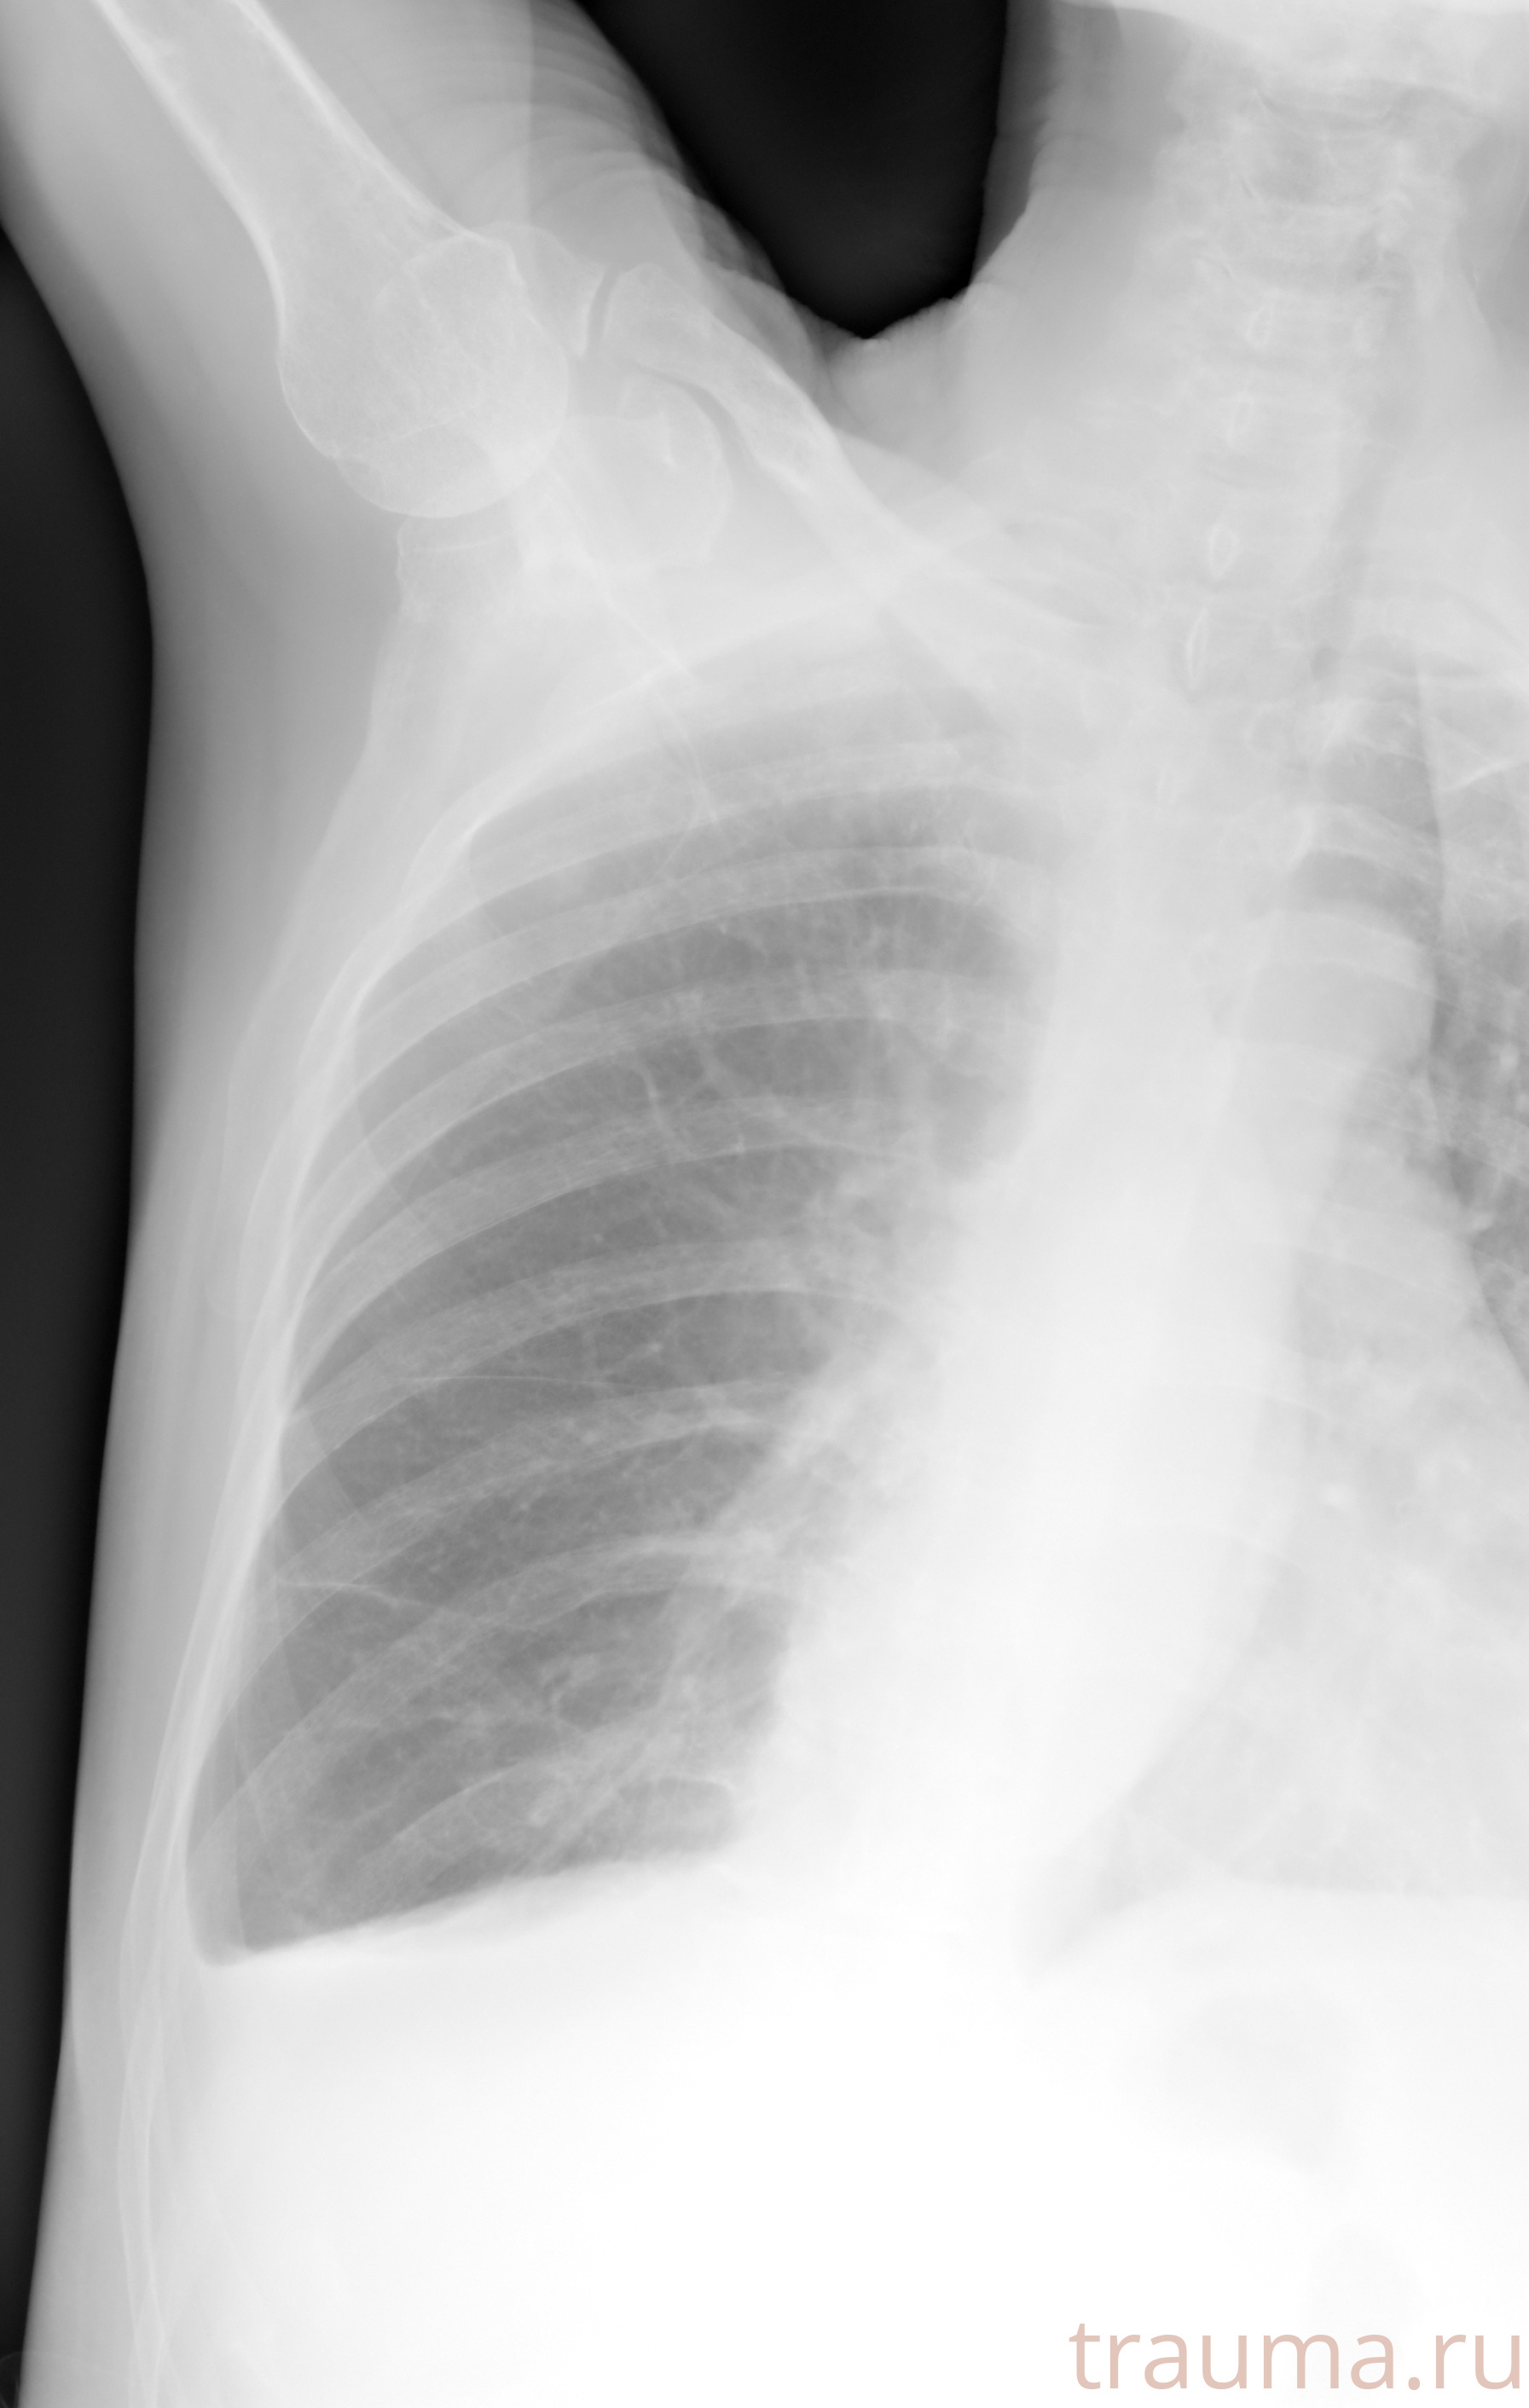

Рентгенограммы

Натуживание 26.12.2025 21:16:34